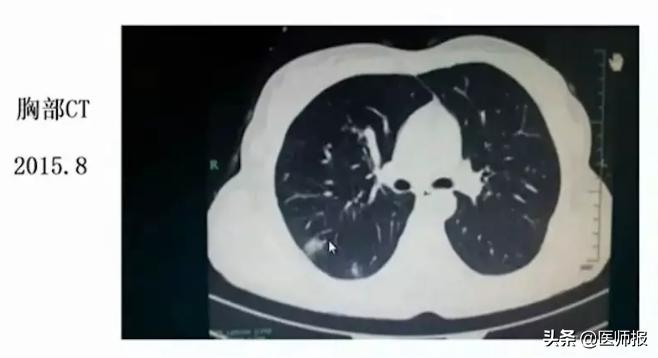

两次胸部CT的结果还是不太一样的,8月份的片子主要集中在右上叶的后段和右下叶的背段,10月份的片子显示明显的病变比原来增加了。